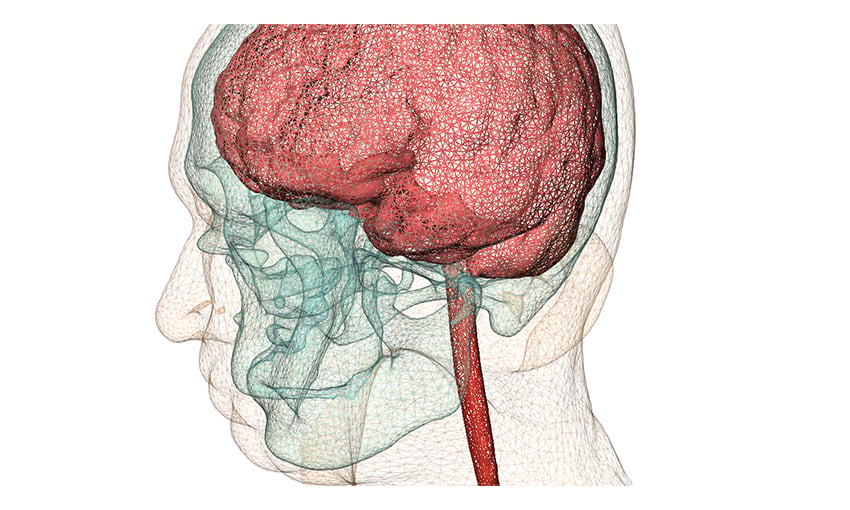

But back to medical-Synopsys has announced that its Simpleware ScanIP Medical software solution is now available to use for medical 3D printing and diagnostic decision-making, as it has officially received FDA 510(k) clearance.Īccording to the FDA, the software’s 510(k) Indications for Use are the following: Its Simpleware software seems tailormade for the medical industry, as it ” offers complete 3D image segmentation and model generation solutions for going from scans to 3D models,” though it can also be used for non-destructive testing and inspection of industrial parts and materials. Synopsys, with its worldwide headquarters located in California and a score of other locations all across the globe, is focused on smart technology, and with more than 30 years in business, I’d say the company pretty well knows what it’s doing.